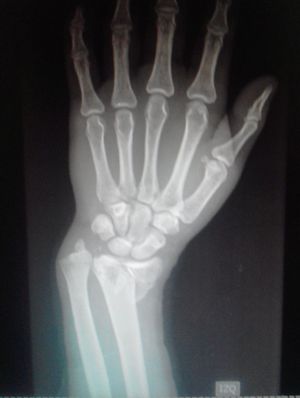

Whats type of fracture is it?

Colle’s fracture

Colle's fracture with distal ulnar dislocation??

Ulnar discloation and distal radius fracture

Colles fracture